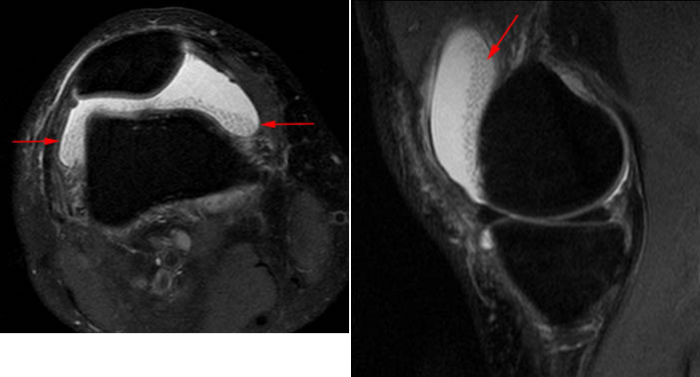

Рисунок 5. PDfs и Т1-взвешенные изображения коленного сустава пациента с ревматоидным артритом. Множественные мелкие «дольки» среднеинтенсивного сигнала на PDfs, которые не визуализируются в Т1ВИ. Они не связаны с синовиальной оболочкой, а свободно «плавают» в толще сустава (помните, что пациент лежит на спине). Эта МР-картина характерна для «рисовых телец» при ревматоидном артрите.

Рисунок 5. PDfs и Т1-взвешенные изображения коленного сустава пациента с ревматоидным артритом. Множественные мелкие «дольки» среднеинтенсивного сигнала на PDfs, которые не визуализируются в Т1ВИ. Они не связаны с синовиальной оболочкой, а свободно «плавают» в толще сустава (помните, что пациент лежит на спине). Эта МР-картина характерна для «рисовых телец» при ревматоидном артрите.

Изоинтенсивный МР-сигнал может также исходить от фиброзной ткани, образующей «рисовые тела», которые встречаются при ревматоидном артрите. Они, как правило, очень малы по размеру и многочисленны. На снимке можно увидеть, что «рисовые тельца» свободно располагаются в толще сустава, а не связаны с синовией.

Мелкие костные тела в синовиальной сумке могут имитировать «дольки» древовидной липомы и ярко выделяться на T2WI и PDfs последовательностях. Однако на T1WI-сканах Вы увидите сигнал, соответствующий сигналу от костных структур, а не от жировых тел сустава. Склеротический (низкого сигнала во всех последовательностях) ободок по периферии — дополнительное свидетельство в пользу остеохондральных тел.